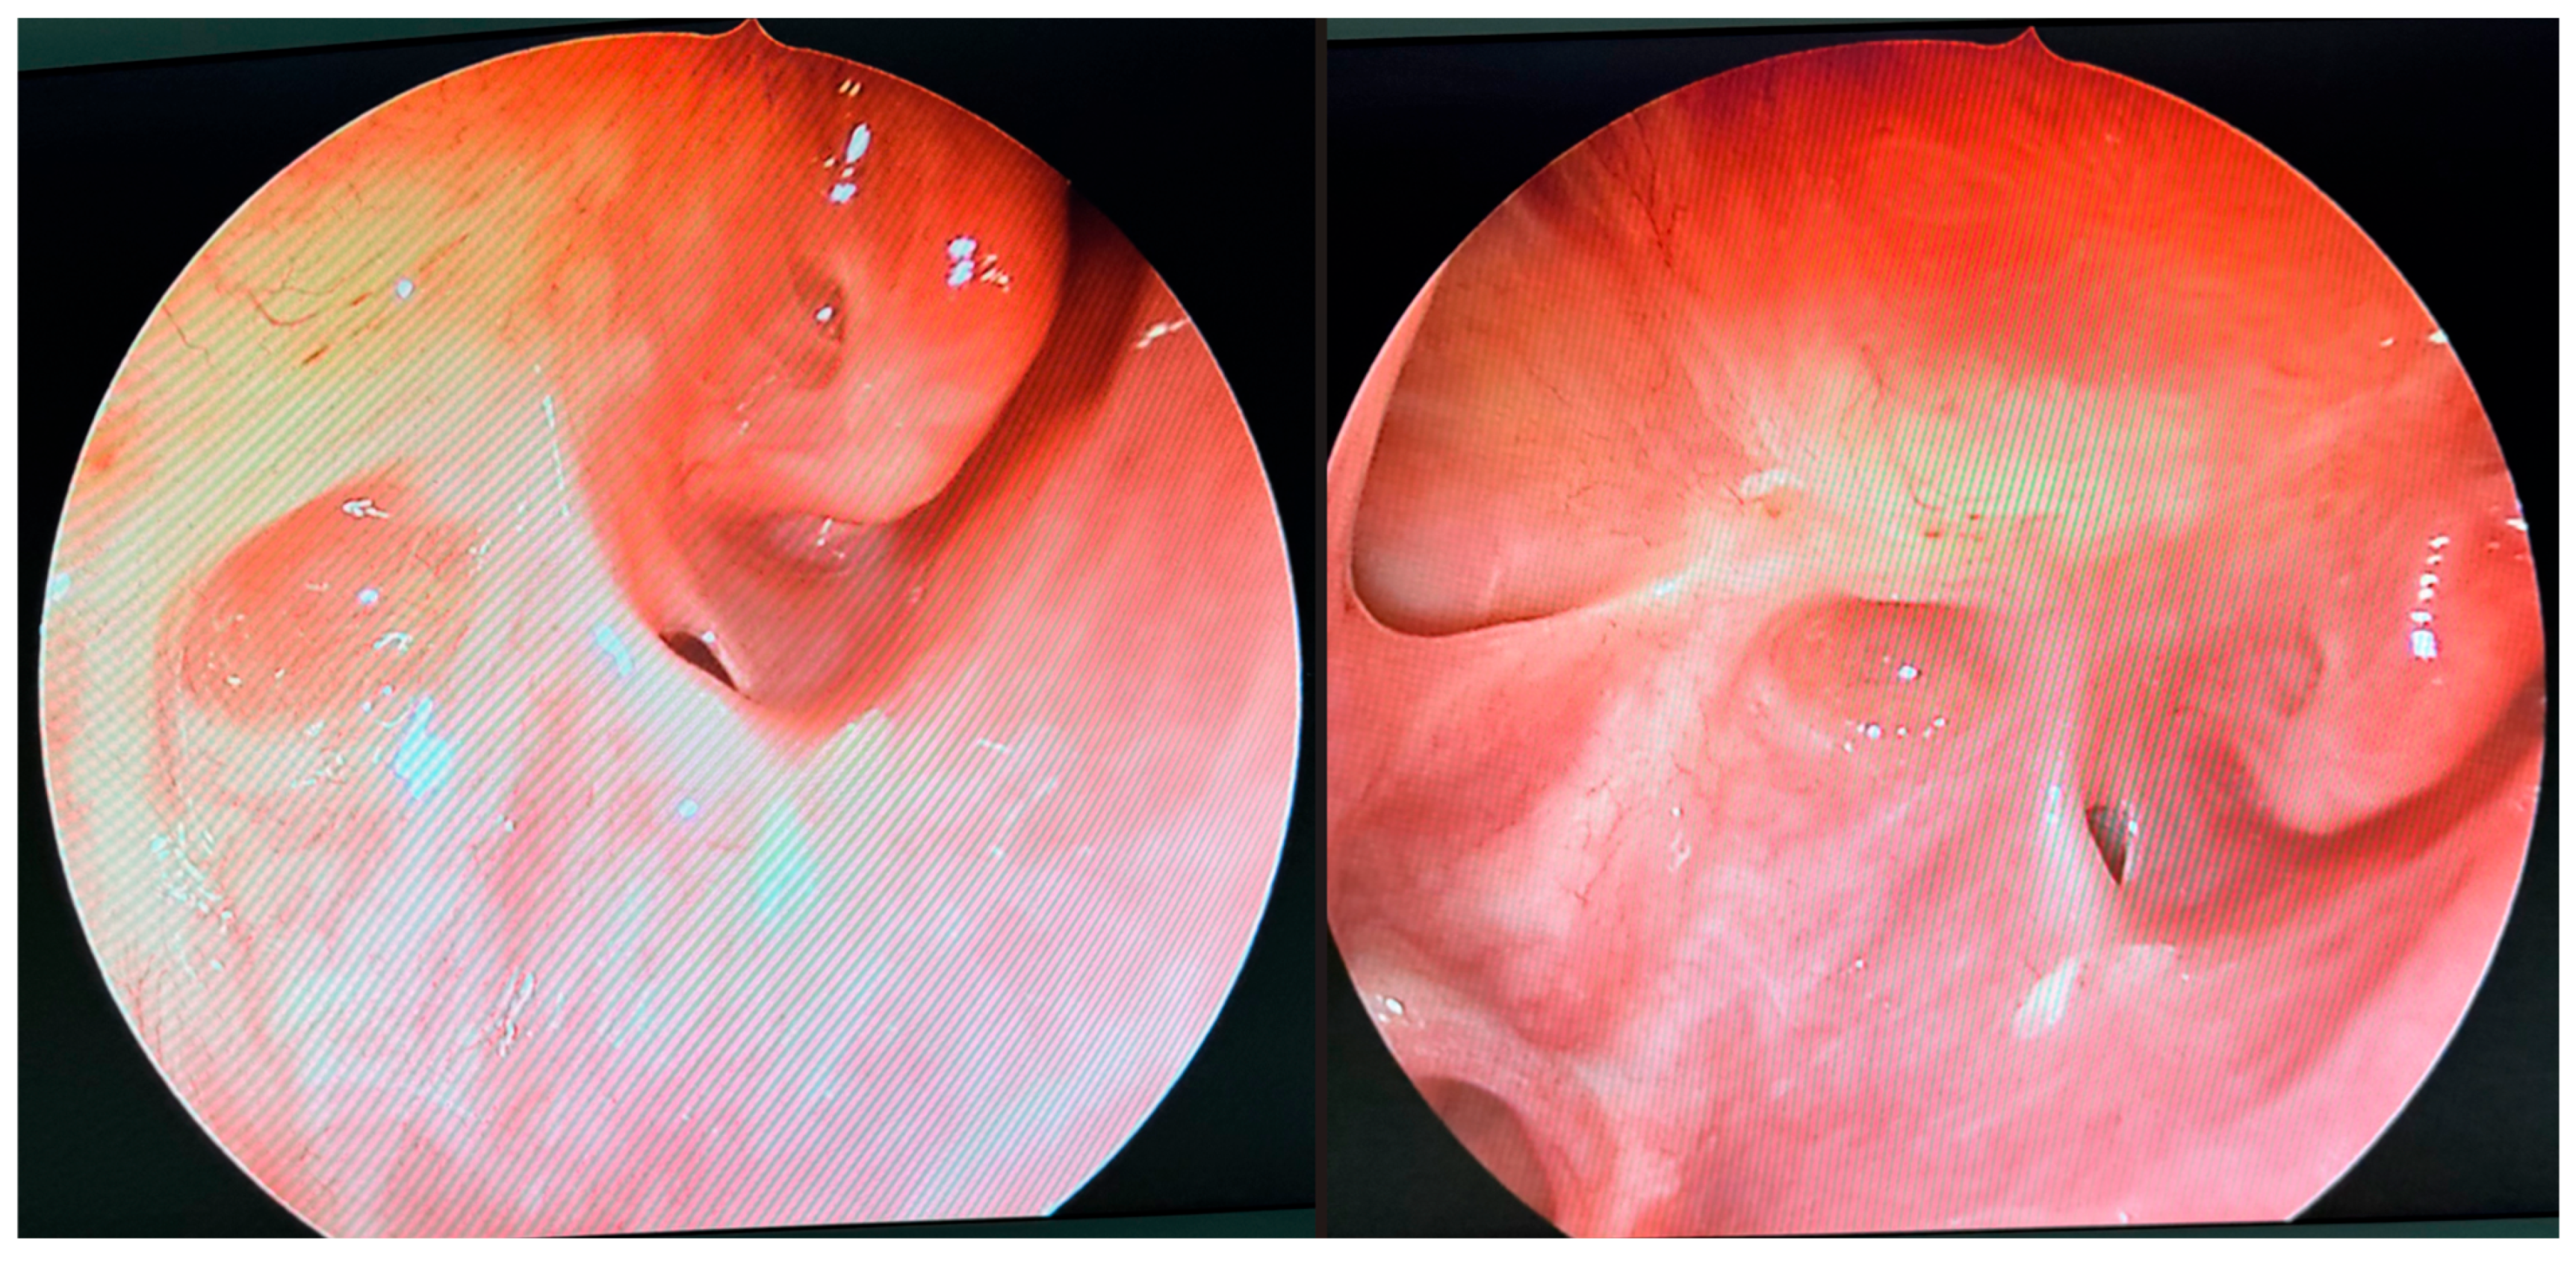

During further inspection, a bony defect of the lamina papyracea was identified in its anterior portion, measuring approximately 4 mm in diameter. The lamina papyracea was resected further, extending posteriorly to the level of the posterior ethmoid cells. A horizontal incision was then made in the orbital periosteum, which allowed for partial herniation of the orbital fat into the ethmoid cavity—facilitating access and drainage. Anterior nasal packing using Merocel was placed to support mucosal healing and maintain patency. Figure 3, Figure 4 and Figure 5 present the intraoperative view.

Figure 3. Endoscopic surgery: intraoperative view showing nasal cavity filled with fungal masses.

Figure 4. Endoscopic surgery: intraoperative view after removal of fungal infiltration to the level of the skull base. Opening of the sphenoidal sinus seen inferiorly (6 o’clock position). The upper-left part of the picture (11 o’clock position) shows the site of orbital periosteum incision with partial herniation of orbital fat into the ethmoid cavity. Two images obtained from the same projection.

Figure 5. Endoscopic surgery: intraoperative view of the right maxillary sinus after removal of fungal masses. Opening of the sphenoidal sinus visible on the right (4 o’clock position).